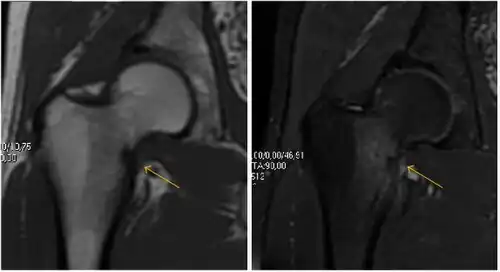

Synovial chondromatosis can be confidently diagnosed by X-ray when calcified cartilaginous chondromas are seen. However, other synovial proliferative processes, such as pigmented villonodular synovitis, require MRI for accurate diagnosis, although noncalcified synovitis can be suspected in radiographs by indirect signs, such as soft tissue swelling and/or erosions in the femoral head, femoral neck, or acetabulum (Figure 7).[1]

Figure 7:

-

Axial CT image of pigmented villonodular synovitis eroding the posterior cortex of the femoral neck.[1] -

Sagittal T2* gradient echo image showing a posterior soft tissue mass with hypointense areas secondary to hemosiderin deposition.[1] -

X-ray of synovial chondromatosis.[1] -

CT of synovial chondromatosis.[1]

In synovial proliferative disorders, MRI demonstrates synovial hypertrophy. In the case of PVNS, characteristic foci of low signal intensity related to hemosiderin deposition are better seen on gradient echo T2* images (Figure 7). In the case of synovial osteochondromatosis, the synovial hypertrophy is accompanied by intermediate signal cartilaginous loose bodies and/or low signal calcified loose bodies.[1]